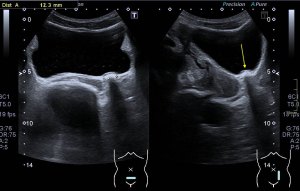

Si colocas la sonda en el mentón, en axial vas a encontrar este músculo Digástrico, que se verá muy bien, superficial, en un plano intermedio tendrás el músculo Milohiodeo y en la profundidad los músculos Geniohideos, Geniogloso y el Hiogloso…Mira:

El Músculo Milohioideo se encuentra en un plano medio, es fino y separa el plano superficial muscular, del profundo, en la imagen superior ves una pequeña porción de este músculo. En el plano profundo un grupo de varios músculos, que he mencionado más arriba y que son músculos extrínsecos de la lengua, situados en la región más medial de esta localización submentoniana estudiada.

Los vientres anteriores de los Músculos Digástricos derecho e izquierdo forman los bordes laterales del triángulo submentoniano, mira: